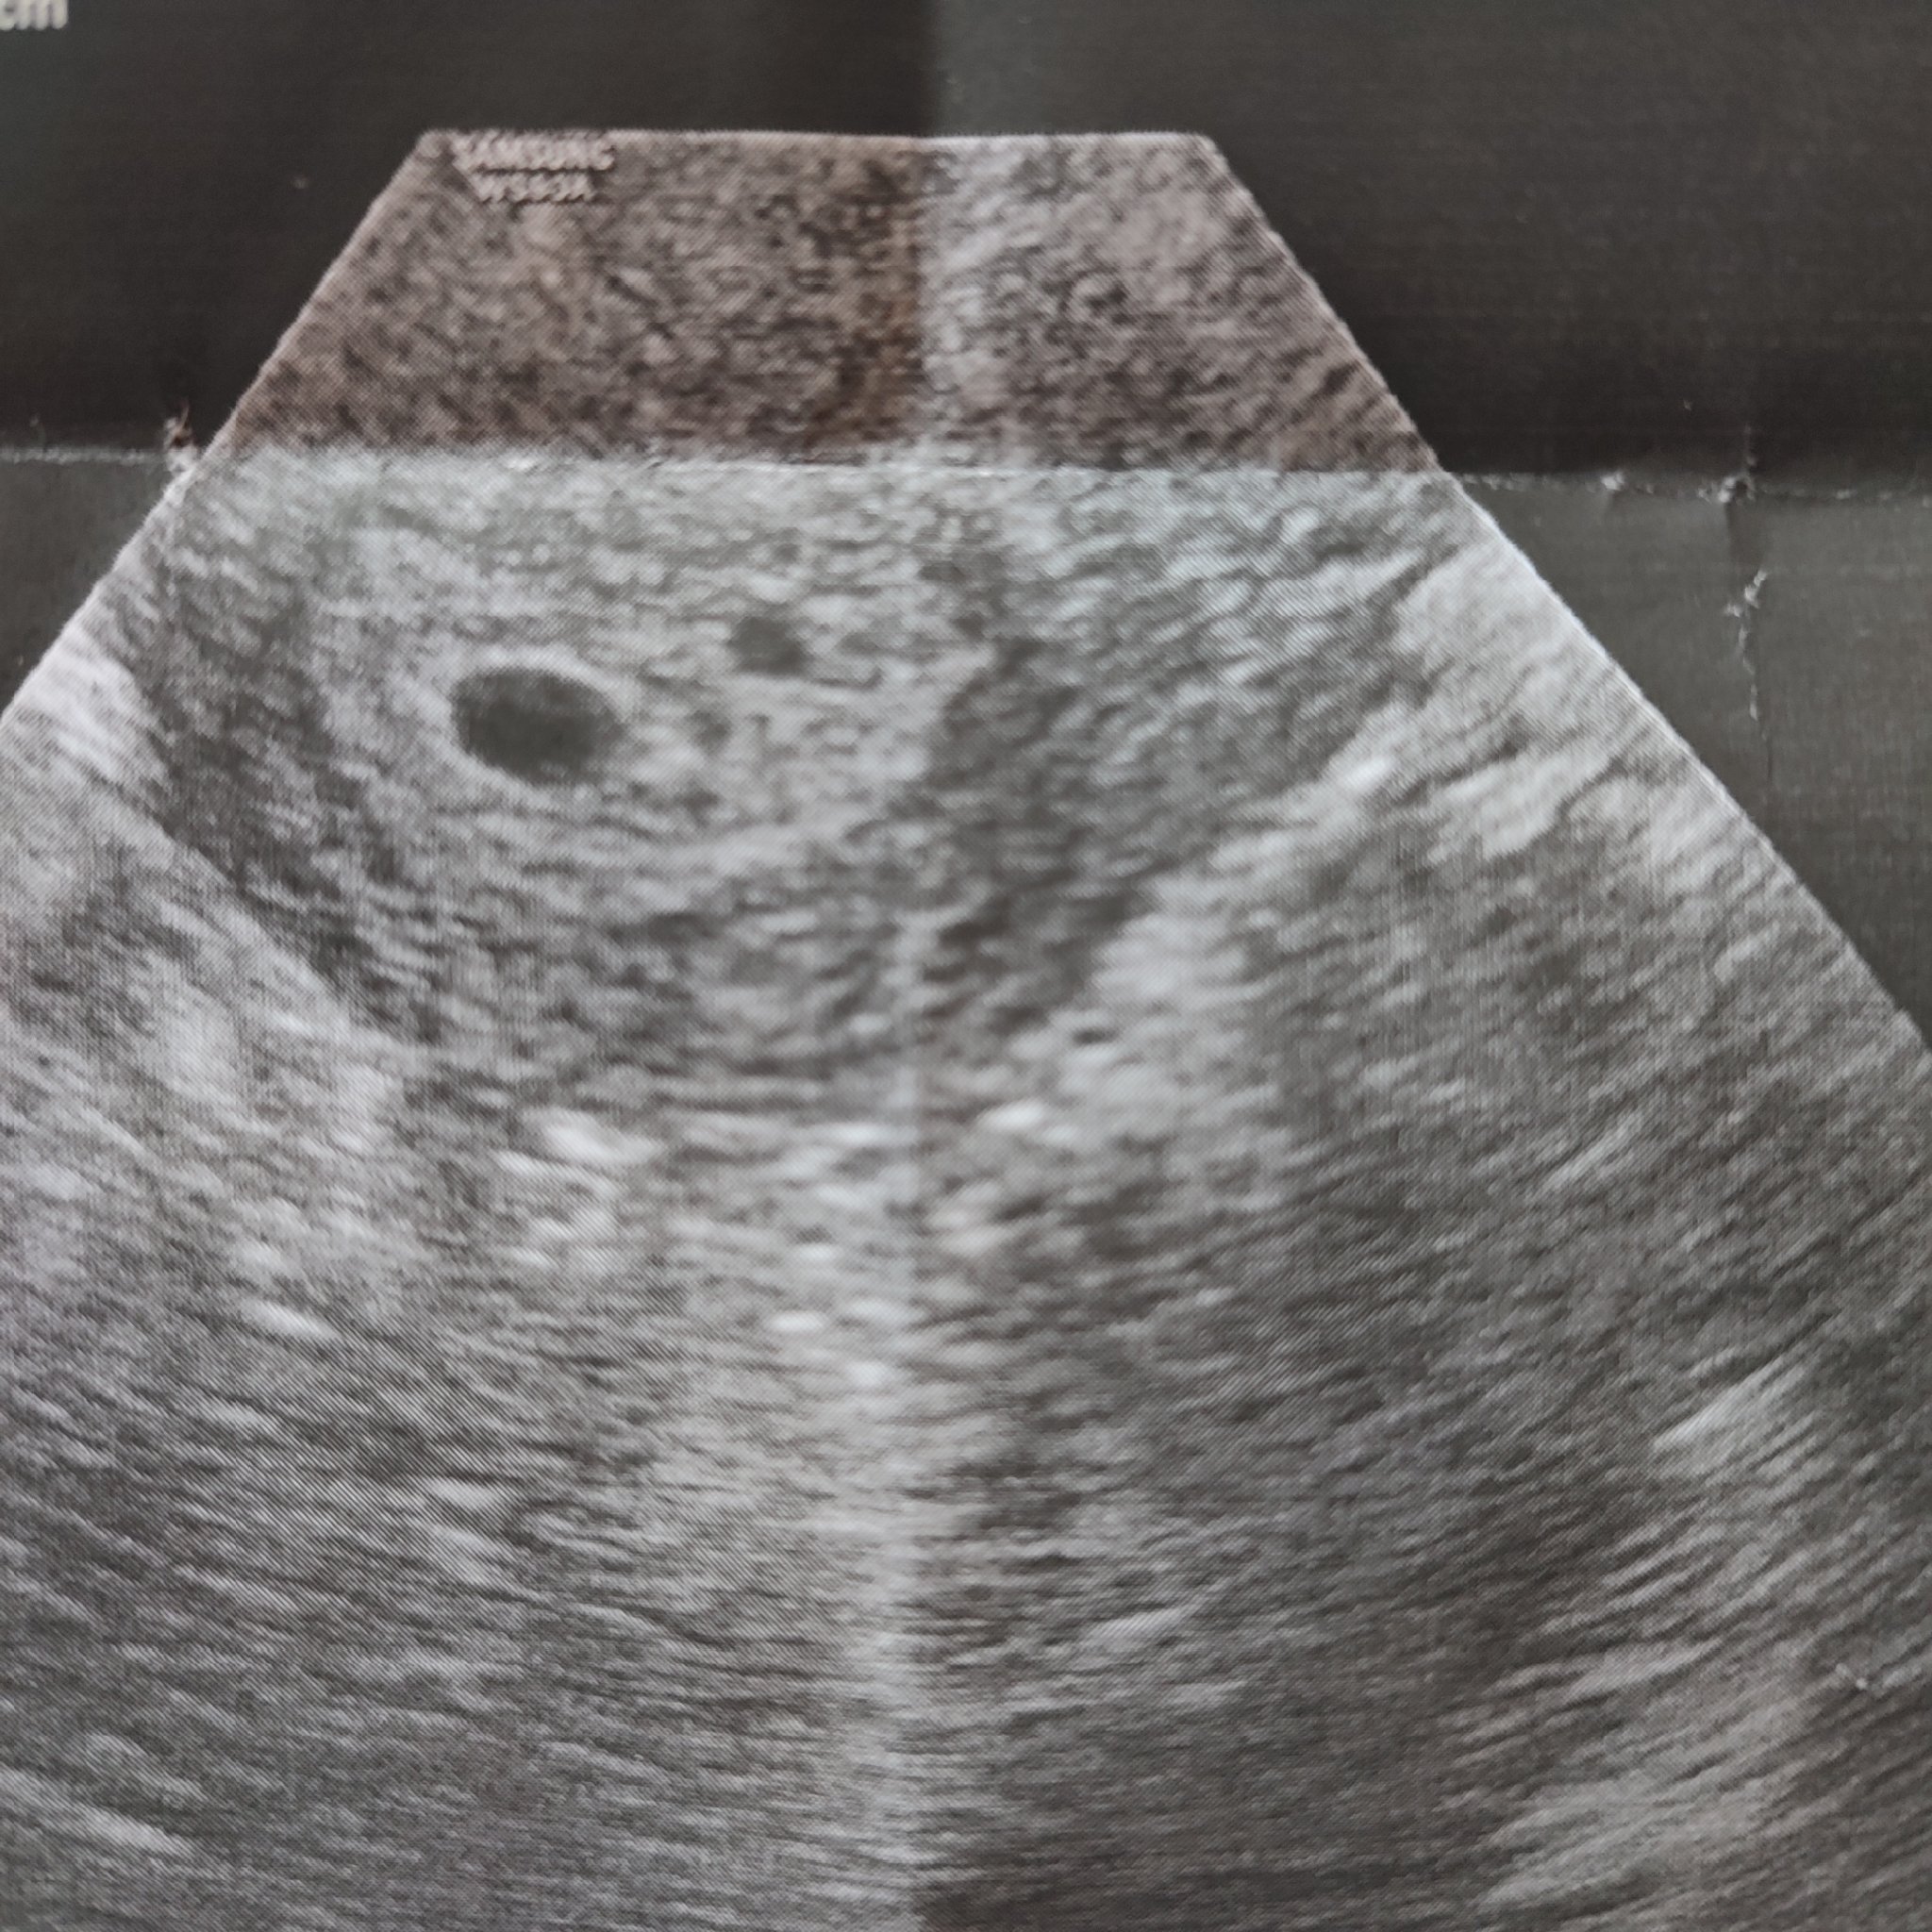

Включвам се в темичката ви с бърз въпрос. Днес бях на преглед за установяване на бременност в 5 г.с. и 1 ден и АГ видя един плоден сак с нормални размери и нещо до него, по-малко, което тя не можа да определи дали е второ сакче или някаква кистичка.

Въпросът ми е може ли втори сак да е толкова по-малък? В рода ми няма близнаци и не очаквам такава развръзка, но ми стана интересно дали при някоя от вас нещата са изглеждали по сходен начин в началото. Прикачвам снимка.

Може да е толкова малък, да. При мен в 5 г. с. се видя само един, в 8-ма бяха два, след няколко дни - 3. В единият не се разви ембрион, така или иначе, но всичко е възможно.